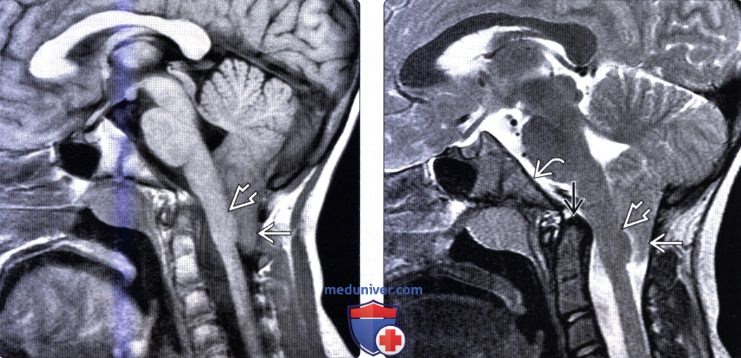

Аномалия Арнольда-Киари: MRI снимки